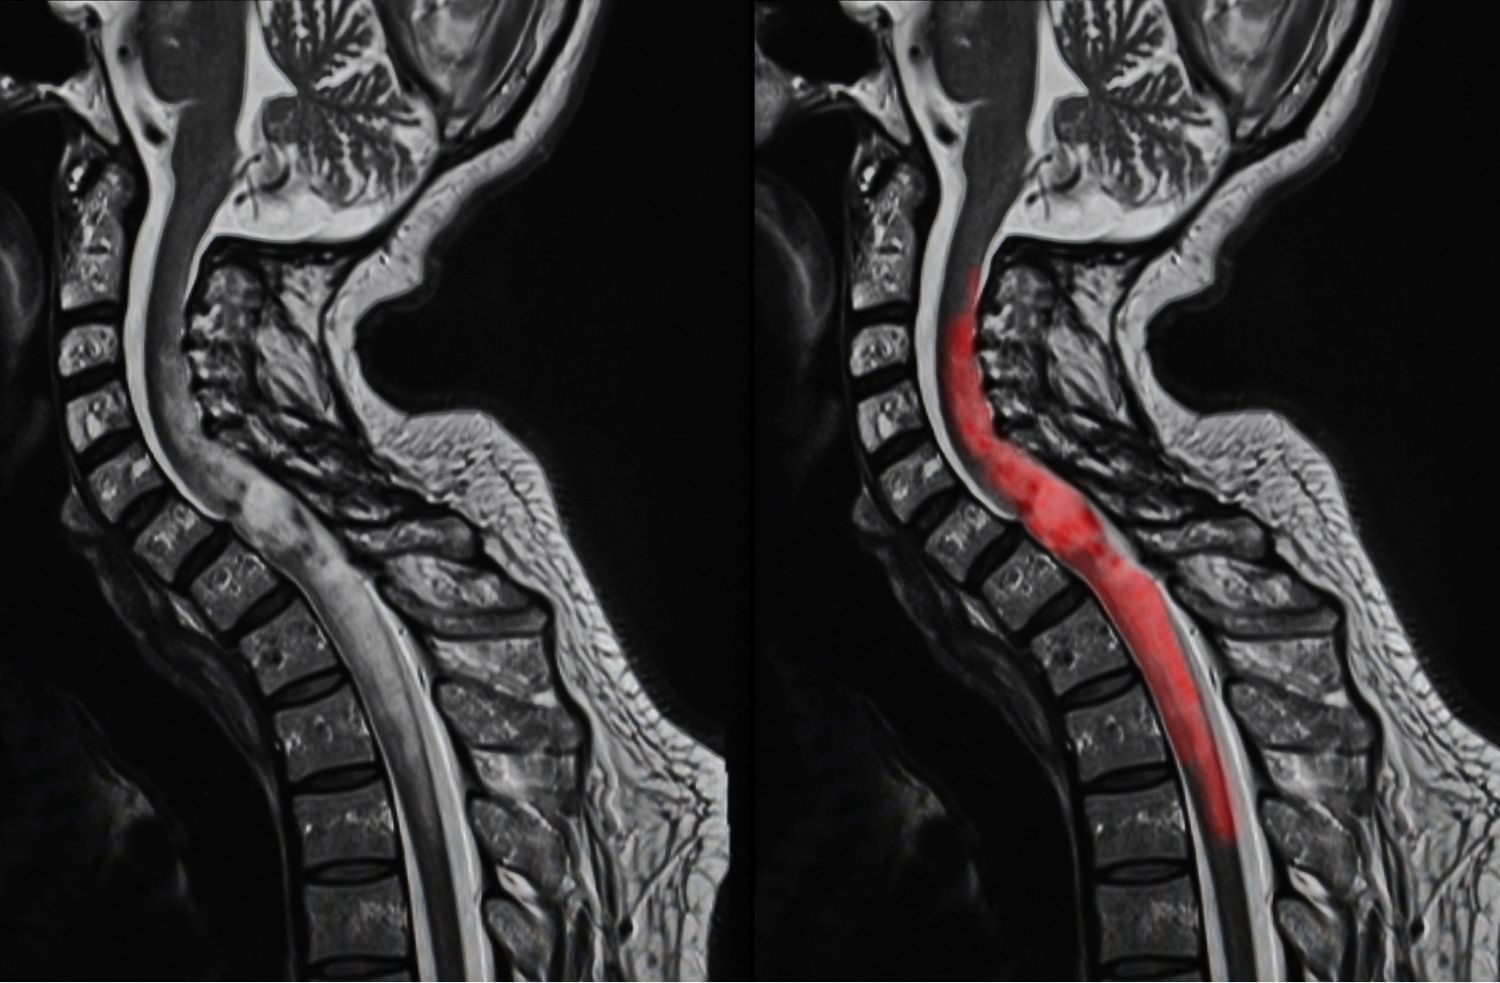

척추관 협착증의 정확한 진단을 위해서는 영상검사가 필요합니다. 대표적인 영상검사로는 X-선, CT, MRI 등이 있습니다. 이러한 검사를 통해 척추의 구조와 크기, 뼈와 디스크의 이상 등을 확인할 수 있습니다.